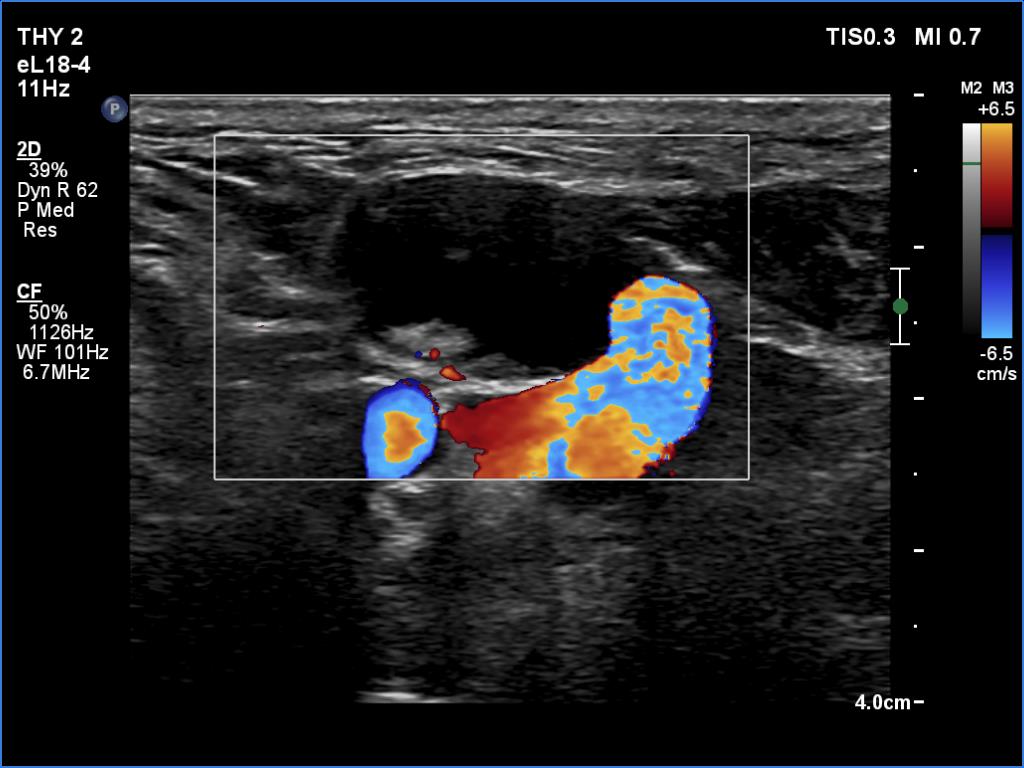

Ultrasonography. The right lobe was echonormal and intact. A large mass occupied almost the entire left lobe. On this side, normal thyroid tissue could only be identified in the dorsal part. The mass was composed of echonormal and hypoechoic areas, had macrocalcifications, irregular intranodular vascularity and proved to be very hard on elastography. There were multiple lymph nodes in III, IV and V left neck compartments. One of the nodes was in close proximity to the jugular vein and was suspicious of having broken into the vessel. The trachea was significantly narrowed at the lower level of the thyroid.

US-guided aspiration was performed from the thyroid mass and from the lymph node presented in the images. Cytology resulted in all three cases in metastatic carcinoma. Wash out thyroglobulin levels were 2.02 and 8.19 ng/L in the thyroid mass and in the neck lymph node, respectively.

2. There are several remarkable findings in this case, e.g., the destruction of the left lobe by the tumor, the elastography pattern, the relation of the largest metastatic lymph node and the jugular vein, the ultrasound demonstration of the trachea' stricture.